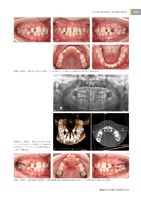

臨床家のための矯正_YEARBOOK2025